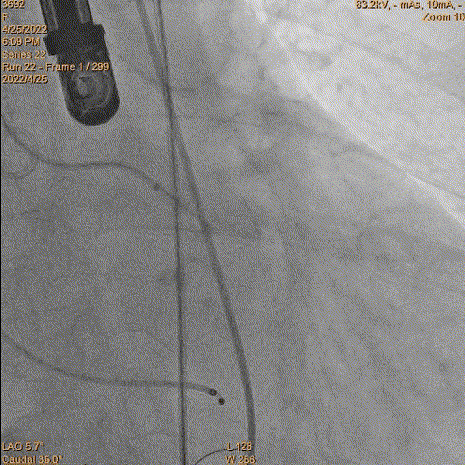

5、瓣膜定位和释放:参考猪尾中段1/3作为起始点。由于猪尾未到达窦底,参考1/2,参考Cusp overlap角度。造影确认位置,开始释放,1/4圈满满释放前1/3,起搏140bpm,压力逐步下降。

瓣膜定位评估

瓣膜释放

评估深度

评估深度-过深